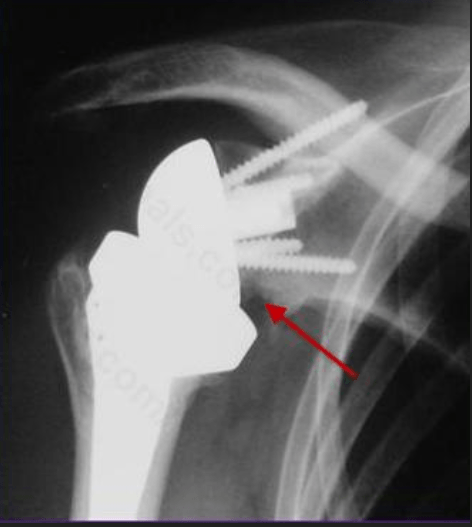

A 78-year old female sustained a 4-part proximal humerus fracture on her dominant side 2 days ago and undergoes a shoulder hemiarthroplasty.  Intraoperatively, the lesser tuberosity reduction was difficult and placed too close to the greater tuberosity, which was anatomic.  What post-operative problem is likely to result due to the position of the lesser tuberosity?

External rotation deficit.

Placing the lesser tuberosity in a more lateral position will increase tension on the subscapularis and likely lead to a deficit in external rotation. Variable outcomes in the prosthetic reconstruction of 4-part humerus fractures often can be attributed to inconsistent and nonanatomic tuberosity placement